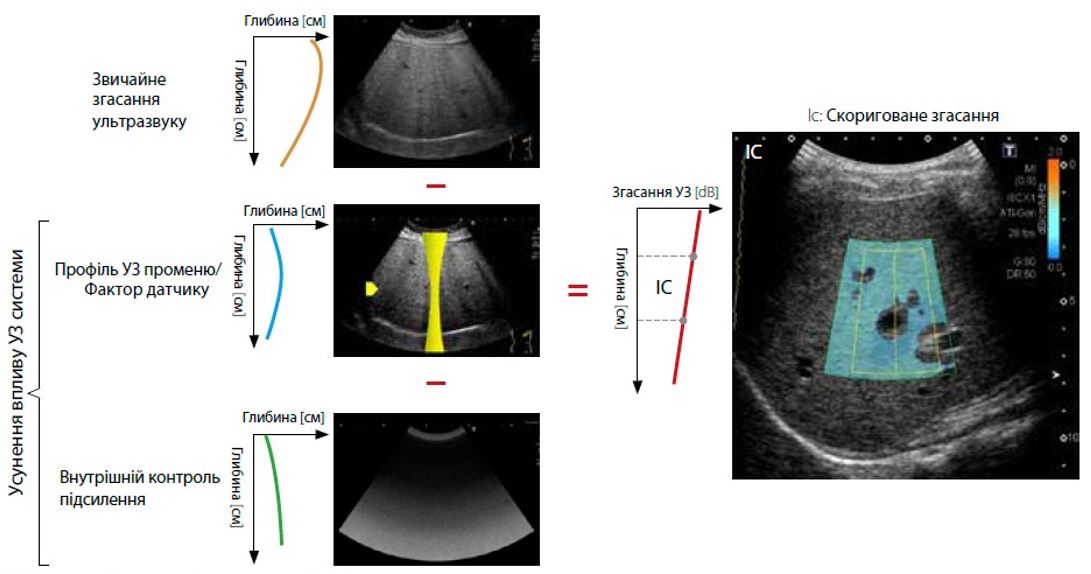

Малюнок 1 Принцип роботи атенюації (ATI)

Принцип ATI

Затухання ультразвукового сигналу залежить від структури тканин і акустичних характеристик паренхіми печінки. Ожиріння печінки пов’язане з підвищеним затуханням ультразвукового сигналу. Через зниження інтенсивності сигналу, особливо в більш глибоких областях, ожиріння печінки часто сприяє отриманню ультразвукових зображень із низькою якістю.

Щоб обчислити коефіцієнт затухання (дБ/см/МГц) за допомогою ATI, вплив системи на затухання сигналу усувається шляхом вилучення залежного від фокуса профілю УЗ променю (дБ) і внутрішнього контролю підсилення (дБ) із звичайного затухання на ультразвуковому зображенні. Скориговане затухання демонструє зміну затухання УЗ в зоні інтересу (ROI).

В ATI зміна затухання демонструється профілограмою. Кожну точку вибірки на профілограмі отримують шляхом усереднення інтенсивності на одній глибині. У пацієнтів із вищим ослабленням сигналу буде більше зменшення затухання, що призведе до більш крутого профілю лінії. Відхилення затухання пов’язане з коефіцієнтом затухання.

Характеристики ATI можна переглянути на зображенні з вимірюванням ATI (рис. 2). Рівень затухання позначається кольором і відображається в ROI. Області зі значними помилками обчислення затухання, такі як структури (кровоносні судини) або області з сильними артефактами (реверберація), виключаються на карті ATI. Оскільки відображаються лише надійні області для вимірювання, точне вимірювання ATI можна отримати швидко та легко. Крім того, коефіцієнт визначення (детермінації) відображається разом із коефіцієнтом затухання, що дозволяє клініцистам підтвердити оптимальне розташування для розміщення досліджуваної ділянки з метою підвищення точності.